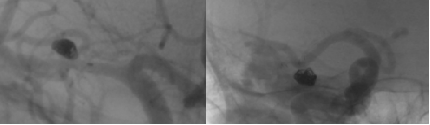

圖一:術(shù)前造影圖

術(shù)后造影顯示,動(dòng)脈瘤未見(jiàn)顯影,手術(shù)圓滿(mǎn)成功。從填塞彈簧圈到最終撤出各級(jí)導(dǎo)管,整個(gè)手術(shù)過(guò)程耗時(shí)較短,操作簡(jiǎn)潔高效,為患者的安全保障提供了有力保障!

圖四:術(shù)后造影